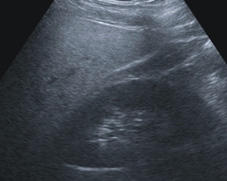

脂肪肝與新陳代謝疾病很有關係。一般以腹部超音波先行診斷,(如:圖一)。如果有三高(高血壓、高血糖、高血脂)則按照上述飲食建議。根據營養學,脂肪肝的人可以常吃背部呈現青色的魚類例如秋刀魚、黃綠色蔬菜(包含:菠菜、南瓜、小白菜、地瓜葉、青椒、秋葵、芥菜、豌豆),選擇白肉魚或雞胸肉、脂肪少的牛肉豬肉。少喝酒、少吃甜食。

圖一、脂肪肝與新陳代謝疾病,以腹部超音波先行診斷